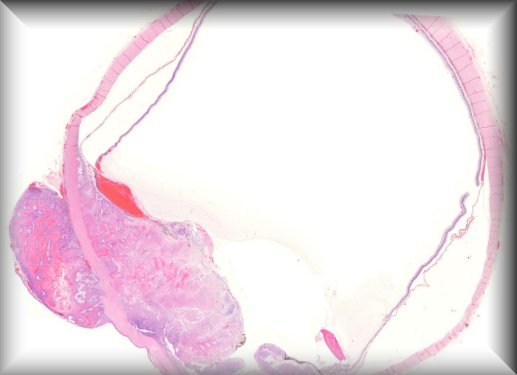

Tero Kivelä (Helsinki): Bilateral anterior segment dysgenesis: sclerocorneal transplantations (slide 1 is from the right eye and slides 2 and 3 from the left eye) |

||